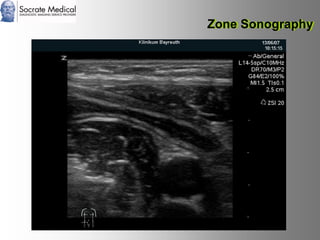

Il documento presenta la tecnologia della zone sonography, che promette una rivoluzione nel campo degli ultrasuoni, superando i limiti dei sistemi tradizionali grazie a metodi di acquisizione dati più veloci e una gestione delle informazioni migliorata. Questa tecnologia consente una maggiore definizione dell'immagine, una riduzione degli artefatti e un'ottimizzazione del processo diagnostico, con vantaggi in termini di tempo e costi. Inoltre, il channel domain processing e la zone speed technology offrono applicazioni avanzate e miglioramenti nella sicurezza diagnostica.